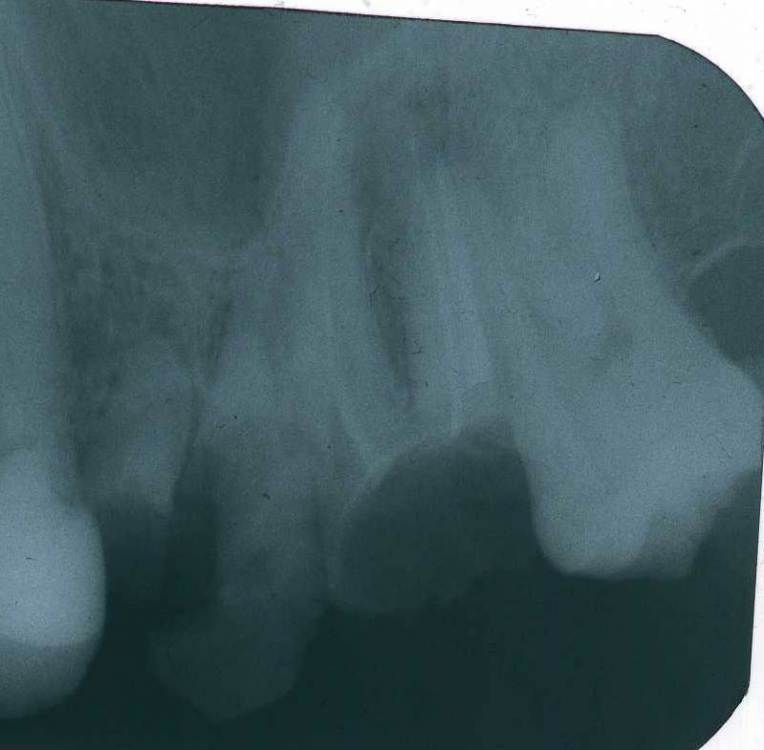

dentt Опубликовано 14 апреля, 2023 Поделиться Опубликовано 14 апреля, 2023 Здраствуйте. У меня вопрос касательно правого верхнего зуба, семерки, перед зубом мудрости. Он был фактичекси полностью запломбирован около трех лет фотополимером, лиш тонкие стенки были. Сама пломба вылетела, эти стенки остались, кроме верхней внешней стенки, что несколько сточилась сейчас. Возможно ли здесь поставить пломбу заново? Позволяют ли корни. Как сделать чтобы пломба какое то время более менее стабильно держалась при небольшой жевательной нагрузки? Ссылка на комментарий

IvanK Опубликовано 15 апреля, 2023 Поделиться Опубликовано 15 апреля, 2023 20 часов назад, dentt сказал: Возможно ли здесь поставить пломбу заново? Здравствуйте, для оценки корней этого снимка не достаточно, в идеале сделать компьютерную томографию восстанавливать зуб пломбировочным материалом нельзя, если корни в порядке, то необходима консультация стоматолога-ортопеда Ссылка на комментарий

dentt Опубликовано 21 апреля, 2023 Автор Поделиться Опубликовано 21 апреля, 2023 Потому, так как вылетела только сама пломба, надеялся что можно хоть временно поставить, но стандартную пломбу. Хоть милиметр-два внешней стенки есть, на снимке она видна серым, полупрозрачном цветом. И хотелось бы знать, как на счет корней, есть там расхождение, или нет? Внизу, они вроде смыкаются. И такое состояние корней было и пару лет назад когда пломба стояла. Ссылка на комментарий

Carioznik Опубликовано 21 апреля, 2023 Поделиться Опубликовано 21 апреля, 2023 У Вас на корнях зуба - есть хроническое воспаление. Если Вы просто поставите пломбу с большой долей вероятности зуб заболит. Чтобы он не заболел , нужно сначала перелечить каналы и только потом поставить пломбу. хорошее лечение каналов займет прилично времени и будет стоить очень не дёшево. Далее, после вылеченных каналов - нужно делать пломбу, в Вашей ситуации, чтобы пломба не вылетела через пару дней-недель -нужен будет ещё штифт. Соответственно цена за пломбу тоже будет не маленькая. Итого: вкладываем много сил и средств в бесперспективный метод лечения ("просто" поставить пломбу). Если Вы готовы прилично пртратится на этот зуб с перспективой удалить его в течении одного до трёх (если повезёт) и найдёте врача , который возьмётся за эту авантюру - то делайте. Ссылка на комментарий

Doc Опубликовано 3 мая, 2023 Поделиться Опубликовано 3 мая, 2023 Даже речи нет ни о каком лечении. Тут корни уже друг от друга отгнили. Что тут лечить? Ссылка на комментарий

Doc Опубликовано 4 мая, 2023 Поделиться Опубликовано 4 мая, 2023 17 часов назад, dentt сказал: На первом из двох фото - видно что есть внешняя стенка. Есть. Одна из четырех. А нужно четыре стенки высотой не менее 1 мм над уровнем десны. 1 Ссылка на комментарий